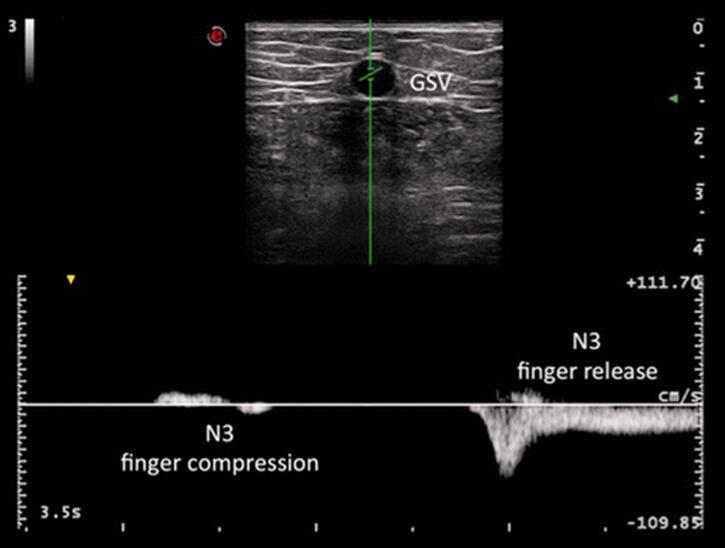

一个简单但真正有效的超声检查能够识别大隐静脉主干上是否存在有效的RP:返流消除试验。2。

功能不全的静脉属支通过手指按压可以消除N3系统穿通支RP点引起虹吸效应图13)。

图13。返流消除试验。一个简单的无功能的属支血流,是赋予自己的RP数字压缩允许区分1型 + N3和3型分流。在大隐静脉返流持续在手指压迫,RP必须保持能量梯度,从而表明穿静脉沿不压缩隐静脉主干(1型 + N3分流)。在手指压迫后返流消失,RP必须将沿着相同的N3支流(为3型分流),用手指压排除在外,所以暂时消除能量梯度。

多普勒超声必须冠状面放置于受检查的大隐静脉RP。如果诱发大隐静脉返流将由N3逃生点受到压缩而消失,能量梯度通过RP向血柱吸入必须考虑无效。因此,处理3型分流,务必避免进行单步骤的高位结扎术(CHIVA1)。正确的处理是进行CHIVA2的第一步骤。

RP可以位于大隐静脉主干和/或功能不全的属支上。如上述报道,一个简单的返流消除试验能鉴别1型之间(1+ N3)和3型分流(图13和图22)。

图22。返流消除试验:功能不全GSV属支出口上方通过PW模式评价大隐静脉(GSV)。由于返流消除试验一个简单手指压迫功能不全的属支,可以有效定位大隐静脉主干上的RP点穿通支,或只是功能不全的属支本身。在本文报道特殊案例,对功能不全的属支进行手指压迫时,一定要小心避免压缩在大隐静脉主干上,在压迫/松开操作时可以检测到血流信号。这一发现证实再入穿通支的存在也沿大隐静脉分布。事实上,再入穿通支的存在是能量梯度维护的原由,允许检测到血流。在大隐静脉主干上没有返回血液的穿通支存在的情况下,不存在能量梯度,也就检测不到血流。当手指松开,位于功能不全属支上的返流RP点,允许出现较大差别的能量梯度,这表现为血流增加。根据返流消除试验,如果在功能不全的穿通支手指压迫的压缩/松弛过程中检测到血流,一个有效的再入穿通支RP点主要位于GSV,可以进行高位结扎(CHIVA1程序)。如果没有检测到血流,正确的做法是对功能不全的属支血流结扎(CHIVA2第一步),因为形成没有引流静脉系统可能导致血栓形成风险,并不遵循CHIVA手术原则。